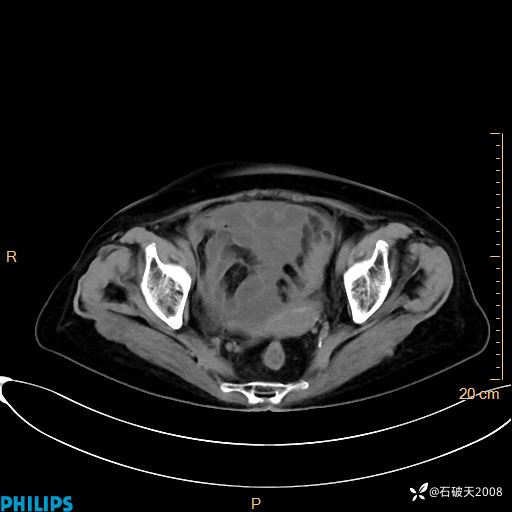

平扫